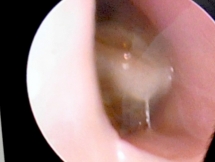

Trẻ nhỏ sổ mũi hôi - Coi chừng có dị vật trong mũi

Mới đây, BS Nhi khoa Trương Hoàng Hưng đã chia sẻ câu chuyện về bệnh nhân nhí chảy nước mũi 2 tuần mà có mùi hôi tới mức mẹ ngủ cùng không ngủ nổi.